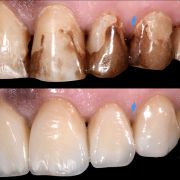

The patient was complaining of heavy stain and multiple faulty restorations. Considering the age in analyzing the teeth shape, contour and color play a vital role in success. Root canal treatment was done for the anterior teeth (Dr Khalid Merdad). Veneers and crowns @perlasmile lab.